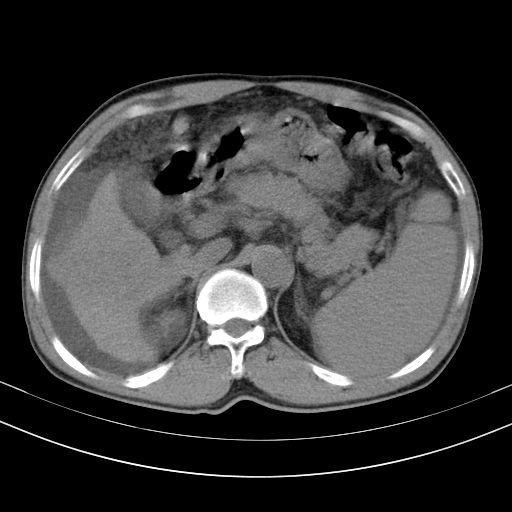

以下是引用随光逐影在2010-2-28 10:23:00的发言:[br]1)考虑肝癌;建议行ct增强扫描检查。2)肝硬化,脾大,腹水。3)慢性胆囊炎。

以下是引用dyqct在2010-2-28 16:44:00的发言:[br][quote]以下是引用随光逐影在2010-2-28 10:23:00的发言:[br]1)考虑肝癌;建议行ct增强扫描检查。2)肝硬化,脾大,腹水。3)慢性胆囊炎。